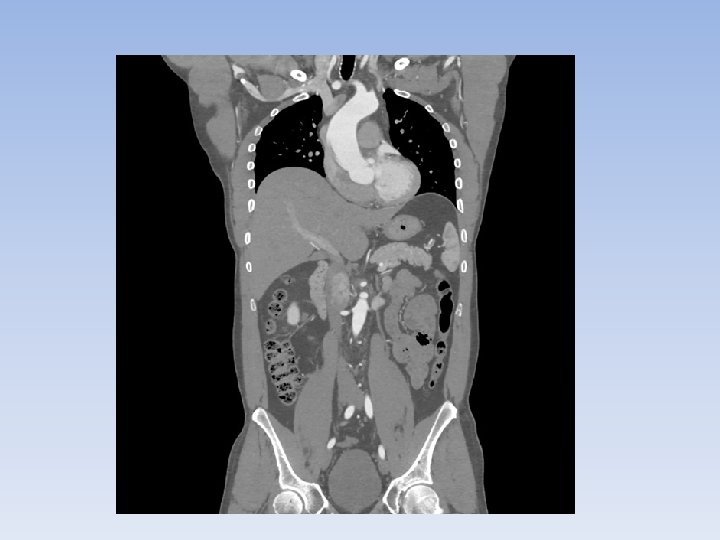

Computer Tomography (CT) Scans • Also known as computer assisted tomography scans (CAT scans). • Uses x-ray equipment to produce 3 D images by taking a series of pictures from different angles. • It is used for diagnosing cancer, skeletal abnormalities, and vascular diseases. • Can be used for imaging bone, soft tissues and blood vessels at the same time. • Used in ERs because it is quick and provides detailed information.